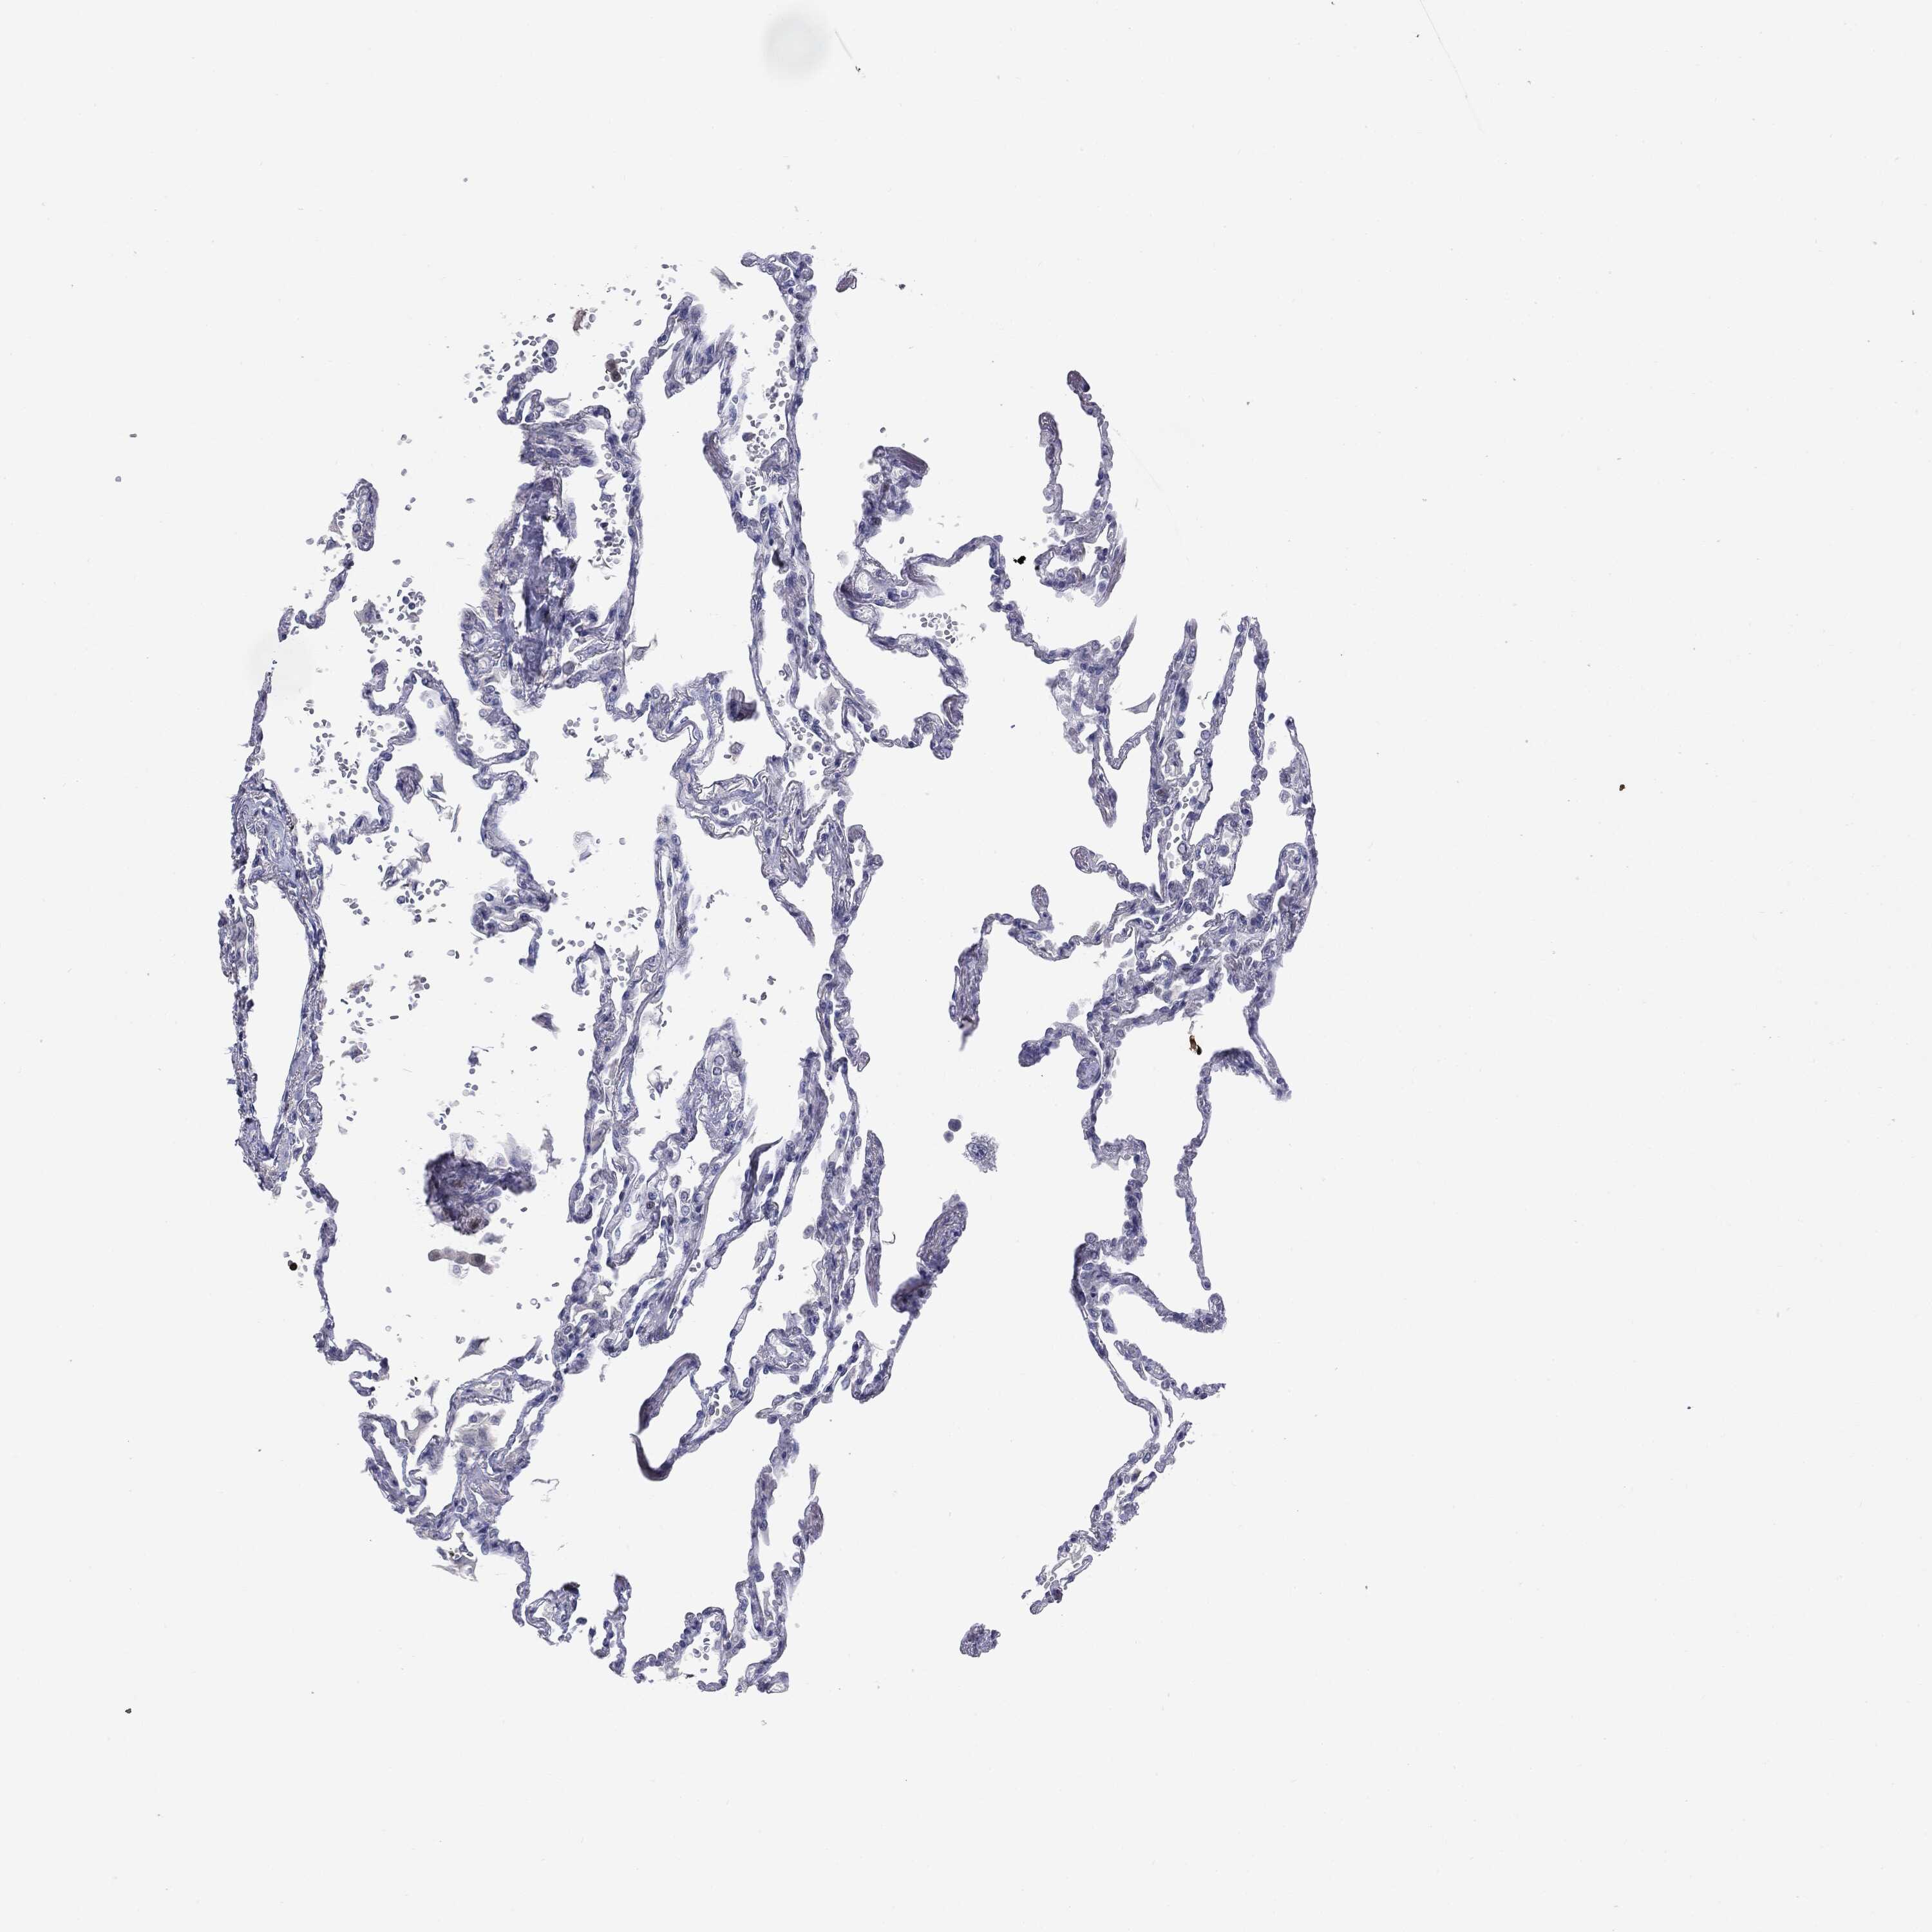

LUNG - Antibody stainingi

Antibody staining in the annotated cell types in the current human tissue is reported as not detected, low, medium, or high, based on conventional immunohistochemistry profiling in selected tissues. This score is based on the combination of the staining intensity and fraction of stained cells.

Each image is clickable and will lead to virtual microscopy that enables deeper exploration of all samples and also displays staining intensity scores, fraction scores and subcellular localization as well as patient and tissue information for each sample.

Antibody HPA059479Antibody CAB000027Antibody CAB000129Antibody CAB080101

Alveolar cells Not detectedNot detectedNot detectedNot detected

Macrophages Not detectedNot detectedNot detectedNot detected